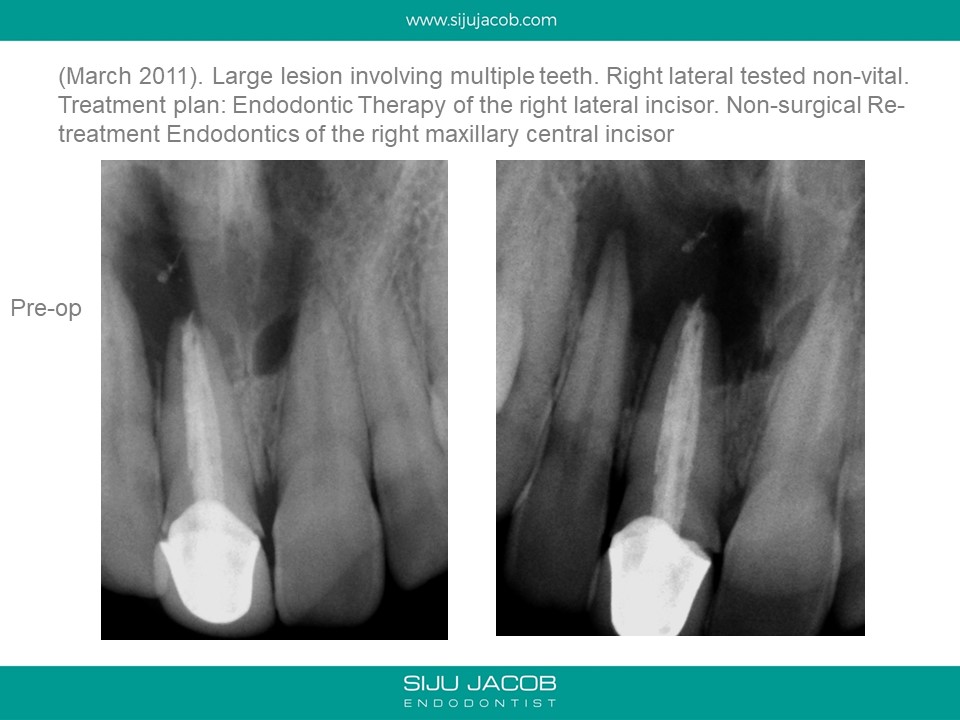

This patient presented with a large lesion associated with a previously endo treated central Incisor with a open apex. The adjacent lateral tested non-vital. I did Endo on the lateral incisor. In the central, I decided to pack Calcium hydroxide till the lesion shrank in size before obturating with MTA. The plan was to keep the original crown in place till there was some evidence of bone fill. The patient disappeared for two years and came back with the lesion completely healed and a solid barrier formed apically through Apexification. I obturated with Gutta percha (No MTA needed) and Advised new crown